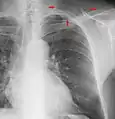

![]() A normal posteroanterior (PA) chest radiograph of someone without any signs of injury. Dx and Sin stand for "right" and "left" respectively. | |